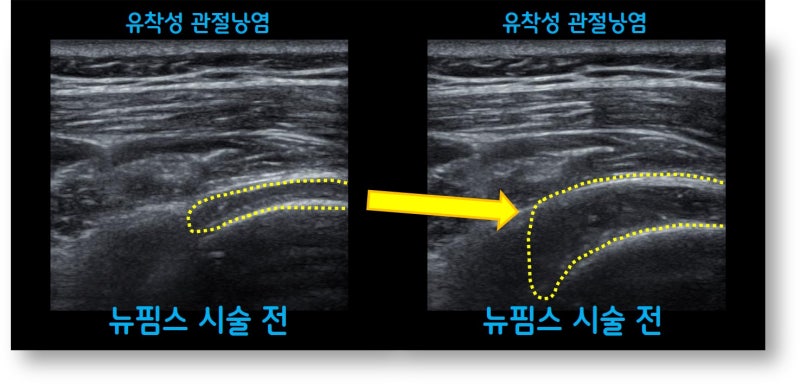

오랜기간 통증이 있어 왔으며 타병원에서 주사치료 및 도수치료를 수차례 했음에도 증상이 좋아지지 않아 뉴핌스 치료 (관절낭유착박리술) 를 시행하였습니다.

오십견은 의학적 명칭으로 유착성 관절낭염이라 합니다. 즉 관절낭에 염증이 생기면서 유착이 발생되어 통증이 생기고 가동범위 제한이 생기는 것입니다. 치료를 제대로 하지 않을 경우 가동범위 제한이 풀리지 않으며 통증이 지속되고 일상생활에 지장이 있을 만큼 증상을 유발하게 됩니다. 물론 처음부터 시술을 하지는 않으나 적절한 주사치료 및 재활을 했음에도 증상 호전이 되지 않을 때는 뉴핌스 치료 (관절낭유착박리술) 를 통해 탁월한 효과를 볼 수 있습니다. 오십견으로 오랜 기간 동안 고통을 받으시는 분들에게 탁월한 효과와 병의 치료를 할 수 있습니다.